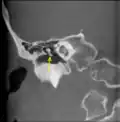

A membrana timpânica direita com o martelo e a corda do tímpano, vista de dentro, por trás, e de cima. (Martelo visível no centro.) | |

Cadeia de ossículos e seus ligamentos, vistos de frente em uma seção transversal vertical do Tímpano. CT imagem de martelo.